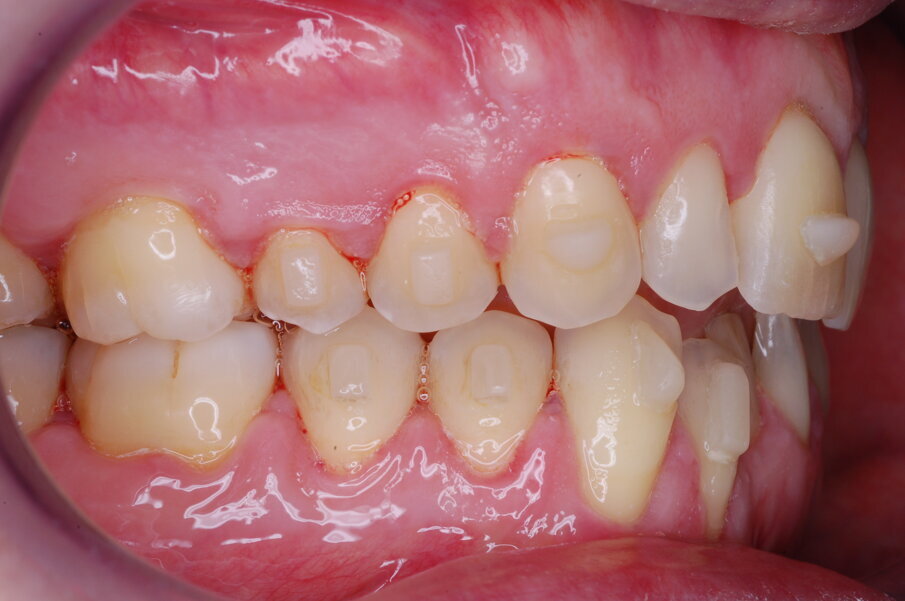

Diagnosi ed eziologia Un uomo sano di 39 anni si è presentato nel nostro studio ortodontico lamentando un aspetto dentale poco attraente e la paura della chirurgia ortognatica proposta da un altro ortodontista. Clinicamente, il profilo del paziente era rettilineo e la vista frontale non mostrava alcuna asimmetria facciale. L’esame funzionale non ha rivelato alcuna deviazione mandibolare o riduzione dei movimenti. Il paziente non aveva dolori articolari e non sono stati rilevati rumori articolari. Era presente una lieve occlusione molare bilaterale di Classe II, un morso aperto e un grave affollamento in entrambe le arcate. L’affollamento era particolarmente grave nell’arcata mandibolare, sebbene mancasse l’incisivo centrale mandibolare destro. Gli incisivi mascellari erano di piccole dimensioni, suggerendo una discrepanza dell’indice di Bolton se fossero stati presenti tutti e quattro gli incisivi mandibolari. Erano inoltre presenti un morso incrociato nella regione dell’incisivo laterale superiore sinistro e una grave rotazione distale del secondo premolare mandibolare sinistro (Figg. 1-8).

Figg. 1-8_Fotografie facciali e intraorali pre-trattamento.